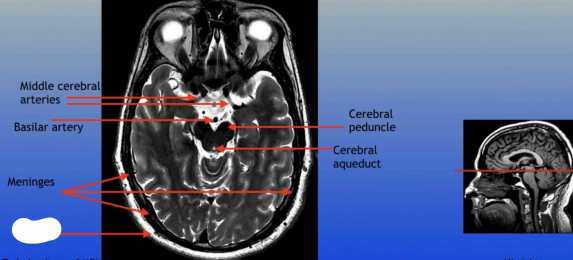

Middle Cerebral Arteries

Basilar Artery

Meninges

Cerebral Peduncle

Cerebral Aqueduct